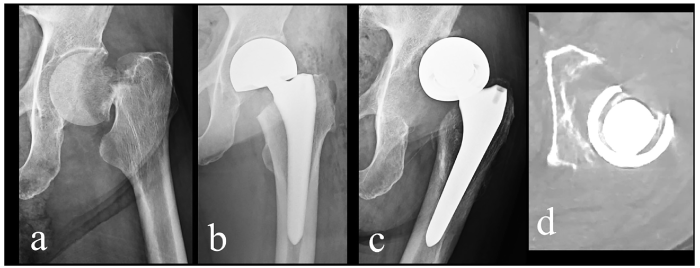

Fig. 1

Fig. 1 Imaging progression.

Plain radiographs of the left hip (anteroposterior view) : (a) At the time of the femoral neck fracture; (b) Immediately after hemiarthroplasty; (c) At 1.5 years postoperatively, osteolysis at the lateral acetabular rim led to superior-lateral displacement of the outer cup. Radiolucent lines were noted around the proximal femur, and the hip was malaligned. (d) Corresponding CT image demonstrated bone loss of the posterior acetabular wall with posterior subluxation.